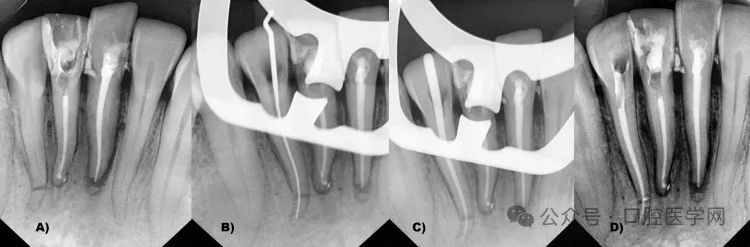

使用Vatech口内传感器拍摄放射片,通过EZ Dent软件(Vatech印度私人有限公司,新德里,印度)阅片(图2)。

a) 右下尖牙长度=30毫米;b) 左下侧切牙29毫米,右下侧切牙28.3毫米,右下侧切牙根尖三分之一水平根折(蓝色圆圈);右下中切牙24毫米,左下中切牙25毫米(冠方断端=24.3毫米,根尖断端0.7毫米),伴根尖三分之一根折(蓝色箭头及圆圈)

影像学分析显示:右下侧切牙(42号牙)根尖三分之一水平根折,根尖三分之一呈远中弯曲,根长超出正常范围(根尖断端3.43毫米,冠方断端24.85毫米)。右下中切牙(41号牙)根尖周损伤(<0.5毫米),总长度24毫米。左下中切牙(31号牙)根尖三分之一小水平根折伴牙周膜增宽,根尖断端0.7毫米,冠方断端24.3毫米,总长度25毫米。左下侧切牙(32号牙)总长度较长(29.3毫米)伴远中扩张。双侧下颌尖牙(43和33号牙)长度约30毫米。